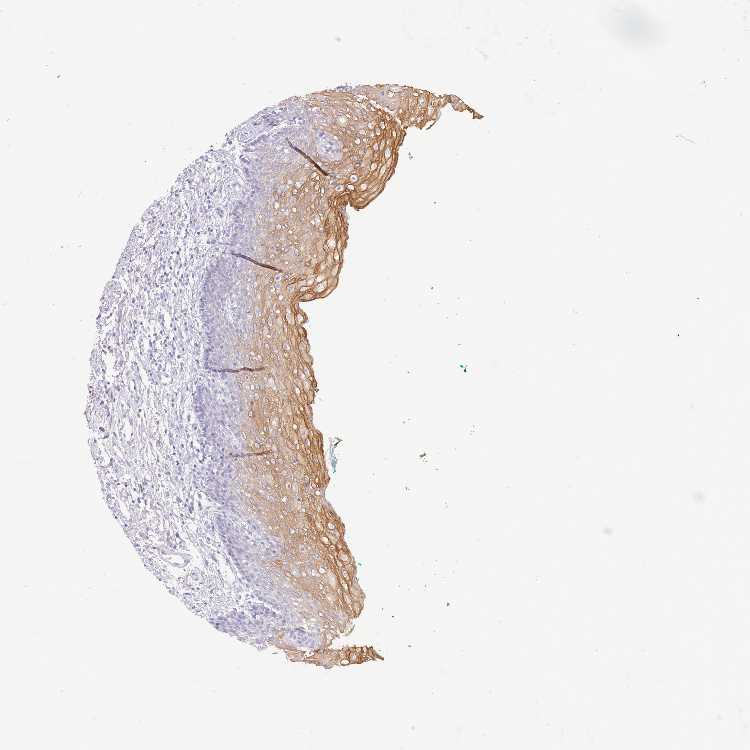

TISSUE PRIMARY DATA ORAL MUCOSA Show tissue menu

ORAL MUCOSA - Antibody stainingi

Antibody staining in the annotated cell types in the current human tissue is reported as not detected, low, medium, or high, based on conventional immunohistochemistry profiling in selected tissues. This score is based on the combination of the staining intensity and fraction of stained cells.

Each image is clickable and will lead to virtual microscopy that enables deeper exploration of all samples and also displays staining intensity scores, fraction scores and subcellular localization as well as patient and tissue information for each sample.

Antibody HPA044158Antibody HPA047913

Squamous epithelial cells Not detectedLow